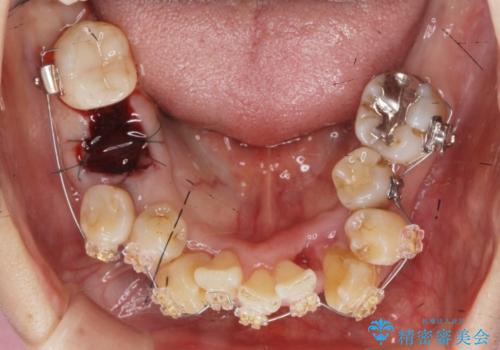

このままの歯並びでは仮にインプラントを埋入したとしても歯ブラシがしづらく、また歯周病の問題が再発しやすい、と判断し矯正治療を行ったのちに歯周病治療、インプラント治療を行っていく治療計画としました。

インプラント治療に加え、歯周病に対しての再生治療や歯周ポケットの除去を行う歯周外科、矯正治療、と必要な治療は多岐に渡りましたが、最終的に安定した噛み合わせを得られたとともに、清掃のしやすい口腔内環境を確立できました。